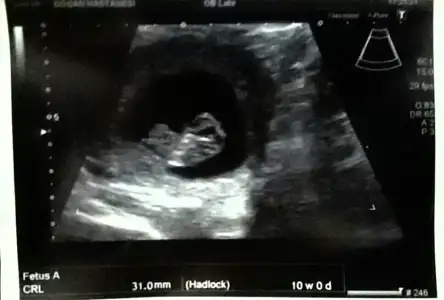

dr soylemeden siz gorun genital nub teorisi ( bebegin cinsiyeti)

[E="neveragain, post: 38969640, member: 400739"]Kızlar buda benim bebegimm önce maşallah diyelim sonra yorumları alayim sizce nedir cinsiyetimiz. :)[/QUOTE]

Evet yorum yokmu kizlar

Kizlar bu bebisim 12 haftalikken